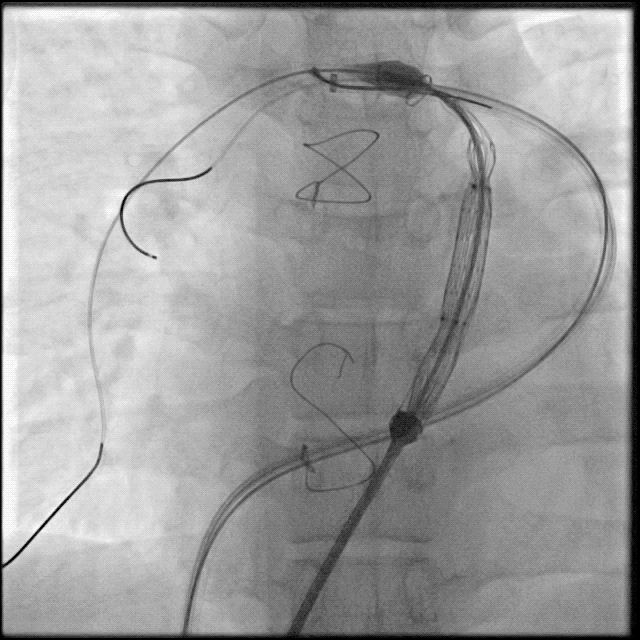

术中球囊压迫试验:

送入超硬导丝建立轨道,送入顺应性球囊,球囊膨胀的同时行左冠状动脉造影,可见冠脉血流通畅,球囊未压迫冠状动脉。